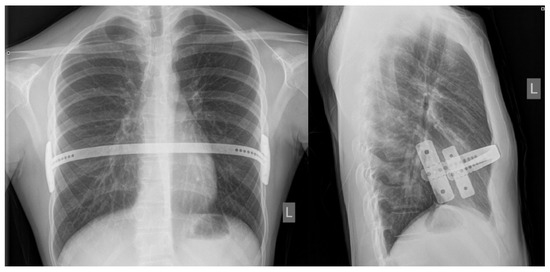

Figure 3.

Bar position at postoperative chest X-ray: posteroanterior (left) and laterolateral (right) views.